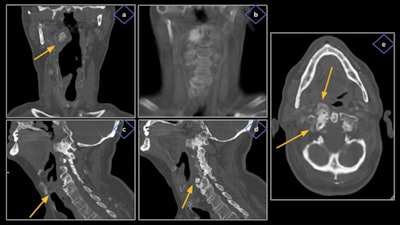

The cross-sectional imaging modality of choice is contrast-enhanced CT, and PET/CT may also have a role. The CT exam must include the upper mediastinum up to the aortopulmonary window and the scan should be acquired during a period of quiet respiration, so the cords are in an abducted position, the authors added.

"The vagus and recurrent laryngeal nerves cannot be directly visualized on CT; therefore, it is imperative for radiologists to recognize their expected courses so we don't miss out on pathologies that may have more significance than the VCP itself," they pointed out.

VCP can be reliably identified on CT due to characteristic findings, although careful evaluation must be carried out by appropriately handling the scan planes of the glottis so potential pitfalls and mimics can be avoided.